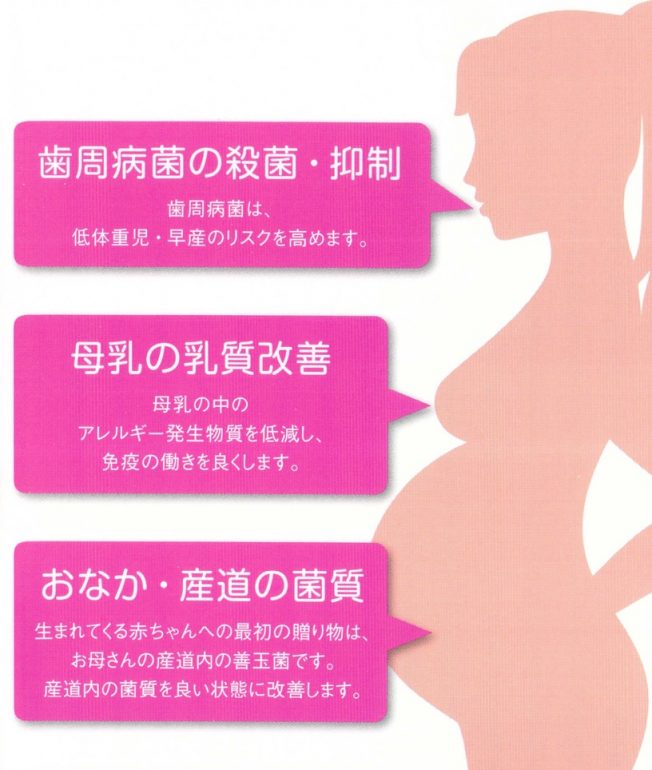

妊娠中や授乳中の方

歯周病菌の殺菌・抑制

歯周病菌は低体重児や早産のリスクを高めるため妊娠中は歯周病菌の殺菌が重要です。

また歯周病菌は夫婦間で唾液感染するため、新しい命を守るために夫婦で歯周病菌を殺菌しましょう。

母乳の乳質を改善

母乳に含まれるアレルギー発生物質を低減し、新生児の免疫効果を高めます。

おなかや産道の菌質

生まれてくる赤ちゃんへの最初のプレゼントは、お母さんの産道内の善玉菌です。

産道内の菌質を良好な状態に改善します。